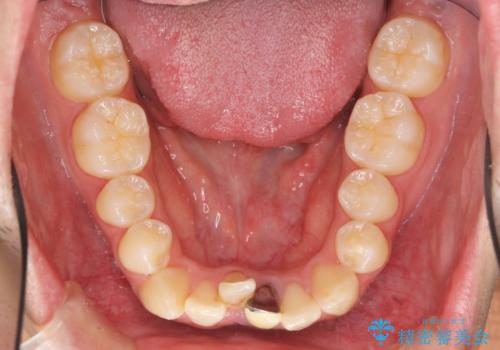

- 前歯のガタガタを主訴に来院。

下の前歯は一本保険治療での被せ物になっており、変色していました。

・神経のない下の前歯を残す

・神経のない歯を抜いてしまって、天然歯で閉じる

のプランを提案し、神経のない前歯を抜く選択をされました。

下の前歯が3本になり奇数になることで、上下の真ん中は一致しませんが、そこまで目立たないと思います。

下の前歯の歯槽骨が一番薄く、歯肉退縮のリスクがあるため、今回のような1本抜歯も選択肢の一つです。